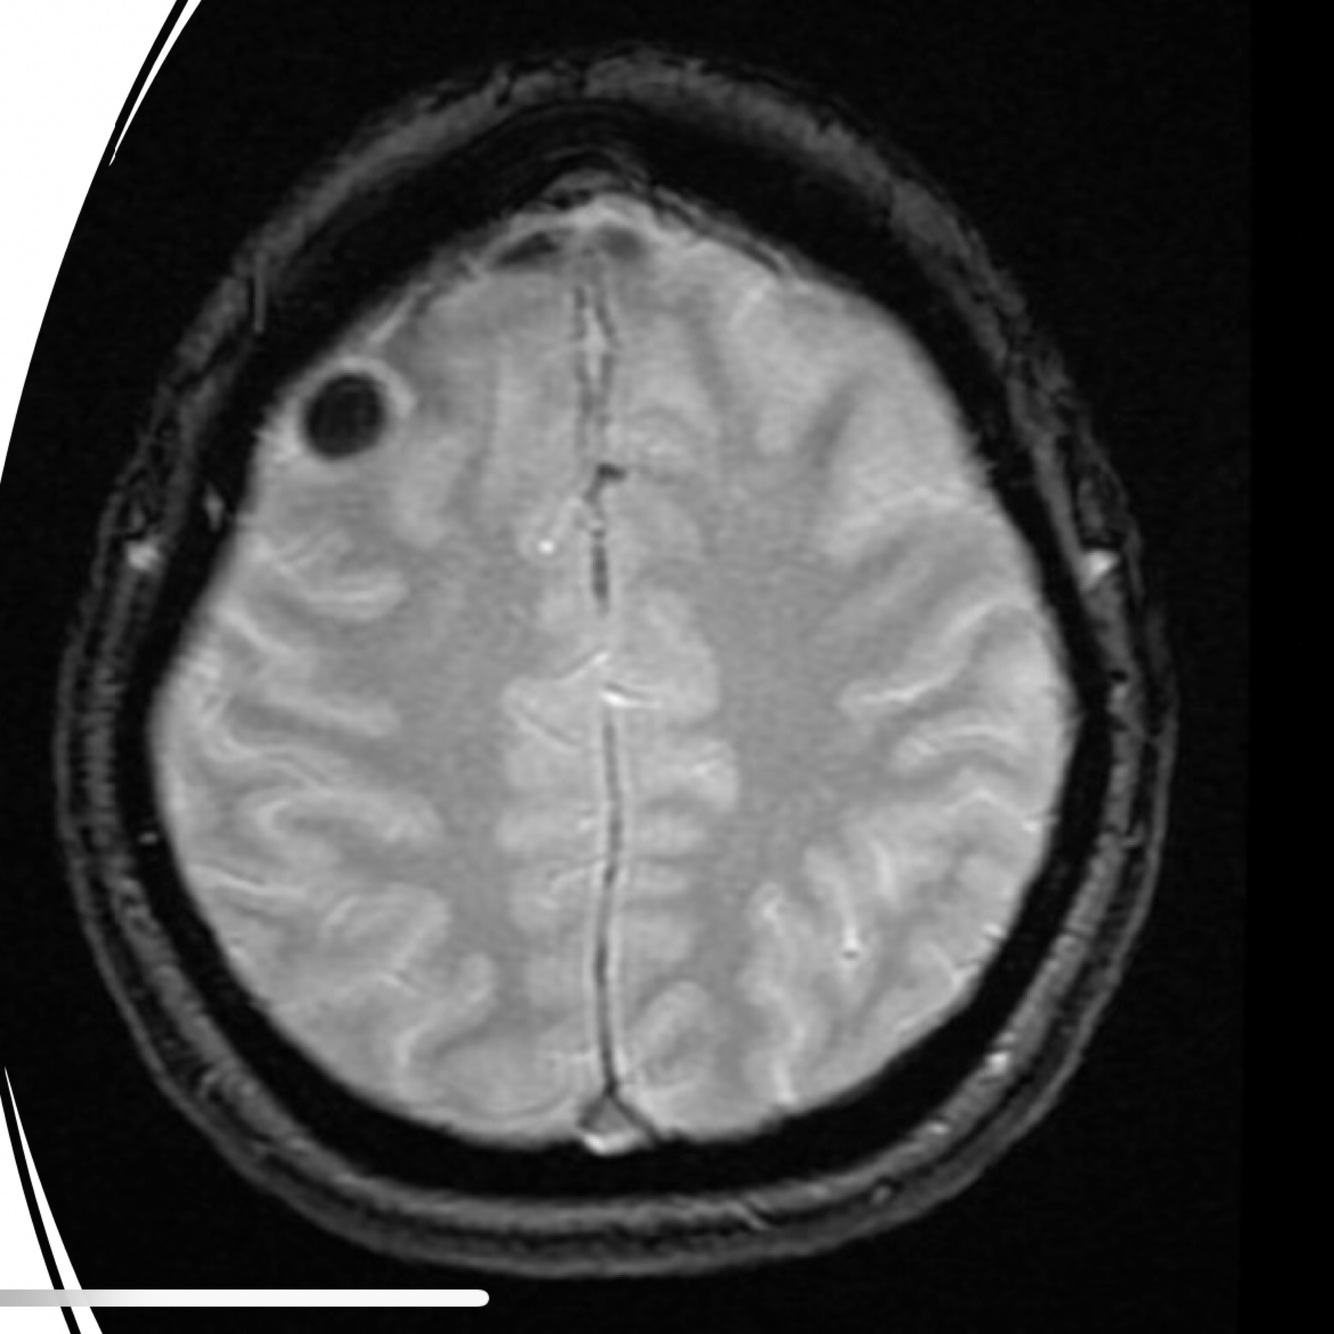

Aliasing on MRI, also known as wrap-around, is a frequently encountered MRI artifact that occurs when the field of view (FOV) is smaller than the body part being imaged. The part of the body that lies beyond the edge of the FOV is projected onto the other side of the image. This can be corrected, if necessary, by oversampling the data. In the frequency direction, this is accomplished by sampling the signal twice as fast. In the phase direction, the number of phase-encoding steps must be increased with a longer study as a result. However, if the FOV and matrix size (phase-encoding steps) are increased and simultaneously number of excitations (or number of signal averages) reduced to half, the imaging time can be kept constant with correction of aliasing. Case 1 demonstrates axial T2-weighted images of the brain that demonstrates aliasing. The first image shows wrap-around with the back of the head projected over the front because the phase-encoded direction is anterior-posterior and the FOV is too small.

Fix: phase and frequency directions reversal resulting in absence of the aliasing artifact. Oversampling is used in the phase direction to eliminate the aliasing.